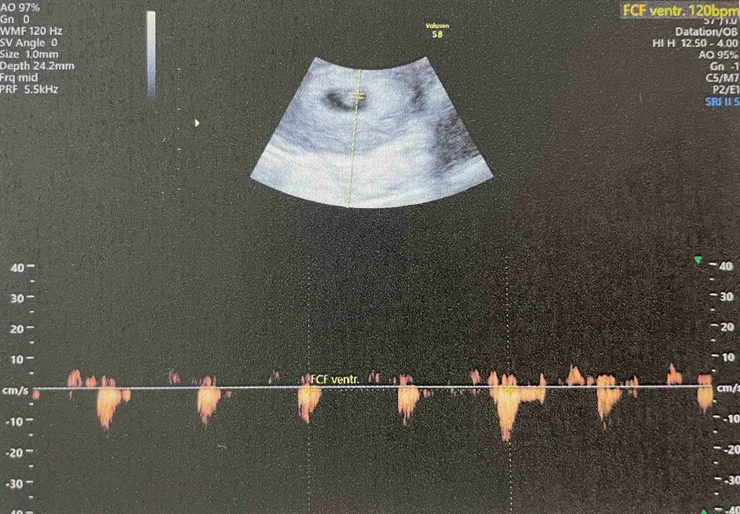

酷酷的女醫生在我的腹部擠上了凝膠,接著把超音波探頭緊貼我的肚皮掃描,前方螢幕上出現了一塊黑影與白點,醫生證實我懷孕了,還確認是單胞胎(後來我們才意識到,原來確認單胞胎或多胞胎對醫生而言是很重要的資訊,難怪不論是法國醫生或者台灣醫生,照完超音波第一句話說的都是「這是單胞胎」),不過因為以最後一次月經來潮日推算才懷孕六週(若以真正精子與卵結合之日計算,胚胎也才四週大),醫生改以內診陰道超音波確認胚胎著床位置與大小。

一時間螢幕顯示了扇形區域,醫生說黑色區域是羊水,白點則是胚胎,測量起來的大小和預期週數差不多。

突然間,醫生把喇叭音量轉開,猶如火車行駛中轟隆隆聲響傳來耳際,我訝異地問著醫生,請問那是心跳的聲音嗎?醫生點點頭,說胚胎以120bpm速率跳動著。